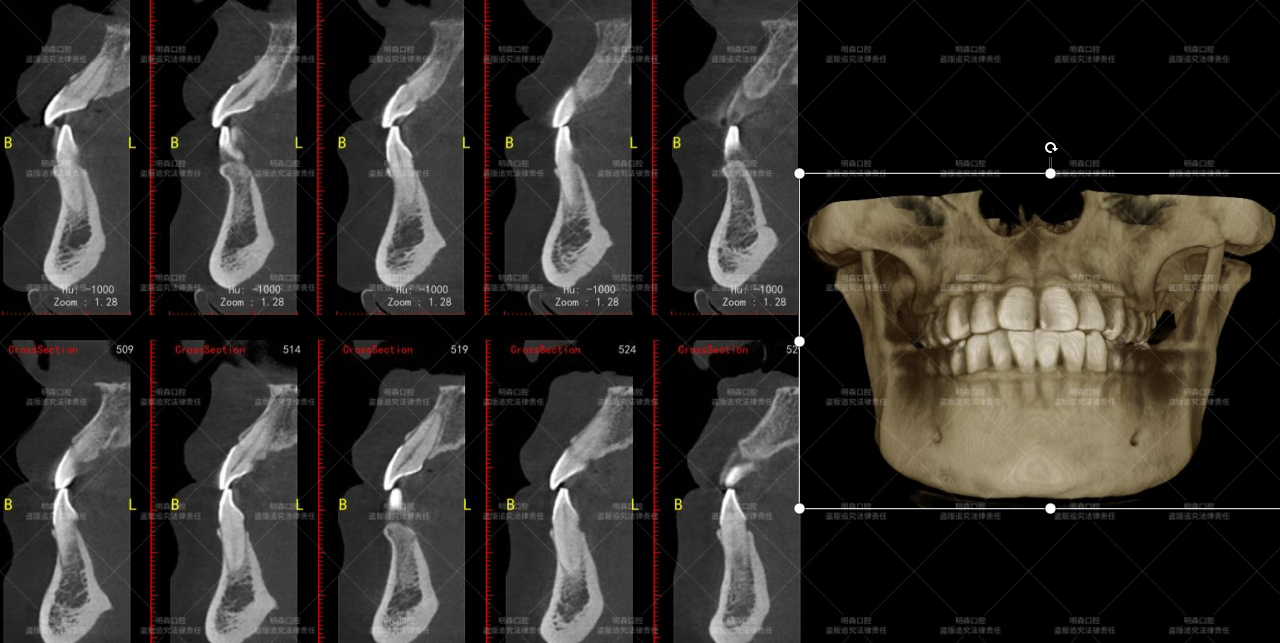

我进行口腔检查时发现,她的11和21 号牙之间宽度足有1-1.5mm,两颗门牙还微微扭转。而且,23 号牙是先天缺失的,好在没有间隙问题,主要困扰还是前牙的“缝隙”。

· 使用先进口腔数字扫描仪获取牙齿三维模型;

使用精细金刚砂车针对11、21号牙进行预备,严格控制磨除量仅0.3-0.5mm(约一张A4纸厚度),局限于牙釉质层保护牙体健康。